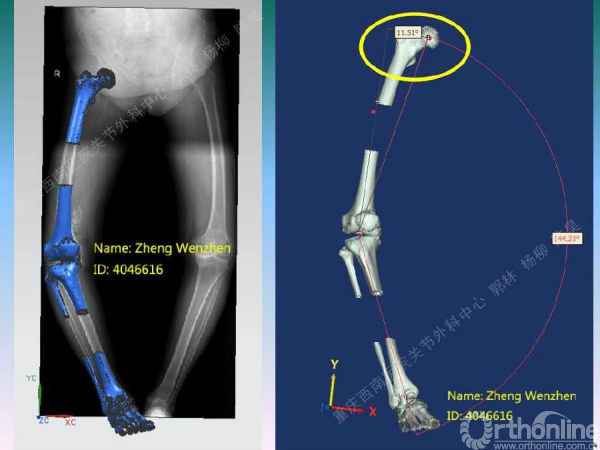

导读:文中,来自重庆西南医院的郭林教授为大家介绍了股骨冠状位关节外畸形的TKA的相关知识,并详细阐述了关节外畸形的概念、诊断、关节内滑移截骨技术等相关内容。

滑移截骨纠正关节外畸形